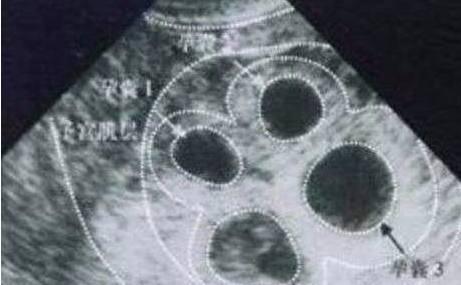

移植2枚冻融胚胎发生单卵单胎合并单卵双胎并

322x217 - 15KB - JPEG